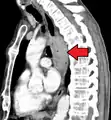

Additional testing is needed to assess how much the cancer has spread (see § Staging, below). Computed tomography (CT) of the chest, abdomen and pelvis can evaluate whether the cancer has spread to adjacent tissues or distant organs (especially liver and lymph nodes). The sensitivity of a CT scan is limited by its ability to detect masses (e.g. enlarged lymph nodes or involved organs) generally larger than 1 cm.[43][44] Positron emission tomography is also used to estimate the extent of the disease and is regarded as more precise than CT alone.[45] PET/MR as a novel modality has shown promising results in preoperative staging with fair feasibility and good correlation in comparison to PET/CT. It can enhance tissue differentiation with lowering the radiation dose to the patient.[46] Esophageal endoscopic ultrasound can provide staging information regarding the level of tumor invasion, and possible spread to regional lymph nodes.

Contrast CT scan showing an esophageal tumor (coronal view)